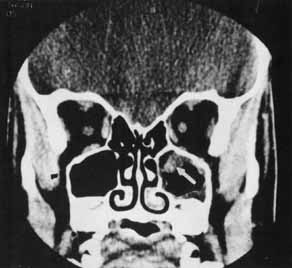

Traumatic optic neuropathy is estimated to occur in 4% of midfacial, supraorbital, or frontal sinus fractures1 and, therefore, should be suspected when there is decreased vision following orbital trauma in absence of globe injury. There will be a relative afferent papillary defect and evidence of orbital soft tissue injury. Visual acuity, afferent pupillary defects, visual fields, and color vision should be ascertained when possible. When damage occurs in the intraorbital portion of the optic nerve, the appearance of the fundus may resemble a central retinal artery or vein occlusion and vitreous, subhyaloid, or retinal hemorrhages may be found radiating from the optic disc.3,4 However, with more posterior damage, the optic disc acutely may appear normal. An orbital CT scan should be obtained with axial and coronal views to assess the integrity of the optic nerve and the presence of an optic nerve sheath hematoma, orbital hemorrhage, or fracture (Fig. 1). The radiologic finding of optic canal fractures may be subtle, and blood in the posterior ethmoid sinus may be the only indication of a fracture with intracanalicular extension.

Fig. 1 CT scan of a fragment of bone extending into the optic canal (arrow).